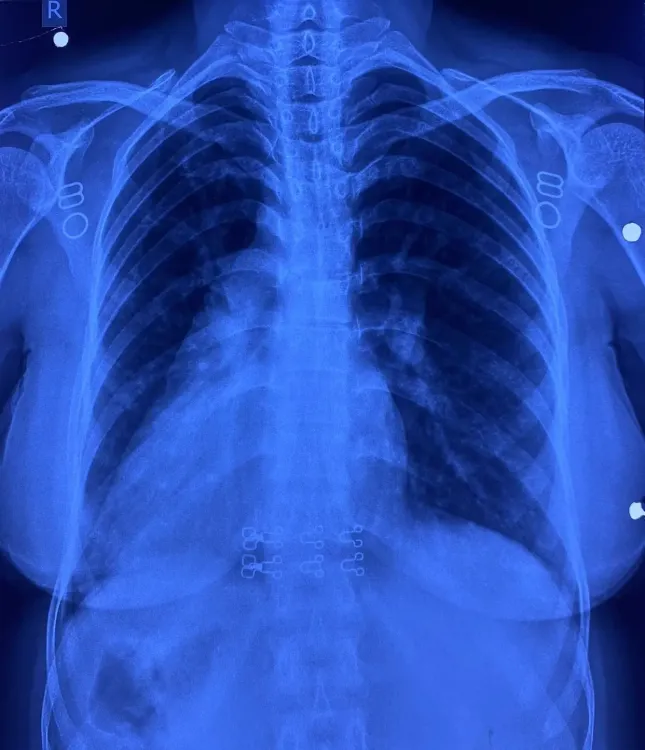

इस मरीज के सभी अंग सामान्य स्थिति के विपरीत थे; दिल दाईं ओर, लिवर बाईं ओर, प्लीहा दाईं ओर, और पेट भी दाईं ओर था। इसके साथ ही, मरीज में जन्मजात आंशिक एट्रियोवेंट्रिकुलर कैनाल दोष जैसी जन्मजात हृदय समस्या थी।

सर्जरी के दौरान, चिकित्सा टीम ने सावधानी से मरीज के हृदय दोष का इलाज किया। मात्र 4 सेंटीमीटर के सूक्ष्म 'इन्फ्रामैमरी' चीरे के जरिए यह जटिल प्रक्रिया संपन्न की गई। ऑपरेशन के दौरान, कार्डियोपल्मोनरी बाईपास मशीन का उपयोग किया गया ताकि हृदय की कार्यप्रणाली सुचारू बनी रहे। मरीज की अपनी 'पेरिकार्डियम' से पैच तैयार कर उसे बारीक टांकों से लगाया गया, जिससे हृदय के वाल्व और कंडक्शन सिस्टम को कोई क्षति न पहुंचे। सर्जरी के बाद मरीज की रिकवरी बहुत सहज रही और अब वह अस्पताल छोड़ने के लिए पूरी तरह से स्वस्थ है। इकोकार्डियोग्राफी ने भी सफल सर्जरी की पुष्टि की।

इस सर्जरी में कई कठिनाइयाँ थीं। सबसे बड़ी चुनौती थी कि जन्मजात हृदय दोष, वाल्व और संवेदनशील कंडक्शन सिस्टम के निकट था। रक्त वाहिकाओं की 'मिरर इमेज' स्थिति ने सर्जरी को और भी पेचीदा बना दिया था। 4 सेंटीमीटर के छोटे चीरे के माध्यम से उपकरणों को संभालना और सूक्ष्म टांके लगाना तकनीकी दृष्टि से बेहद कठिन कार्य था। मरीज को हृदय–फेफड़ों की मशीन के माध्यम से बायपास करना पड़ा, जिससे टीम की विशेषज्ञता और अनुभव की आवश्यकता थी।

साइटस इन्वर्सस अपने आप में अत्यंत दुर्लभ है और इसके साथ आंशिक एट्रियोवेंट्रिकुलर कैनाल दोष होना और भी कम होता है। आमतौर पर, ऐसी सर्जरी में सीने की हड्डी काटनी पड़ती है, लेकिन इस केस में केवल छोटे कॉस्मेटिक चीरे से सर्जरी की गई, जिससे यह दुनिया की पहली सर्जरी बन गई। मरीज रमबाई और उनके परिवार ने डॉ. नरेंद्र सिंह झाझड़िया और पूरी टीम का दिल से धन्यवाद किया।